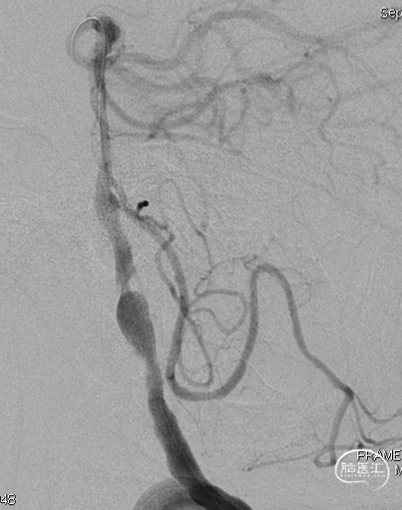

术后即刻DSA。

术后即刻稀释造影:“拉直”可见支架贴壁良好。